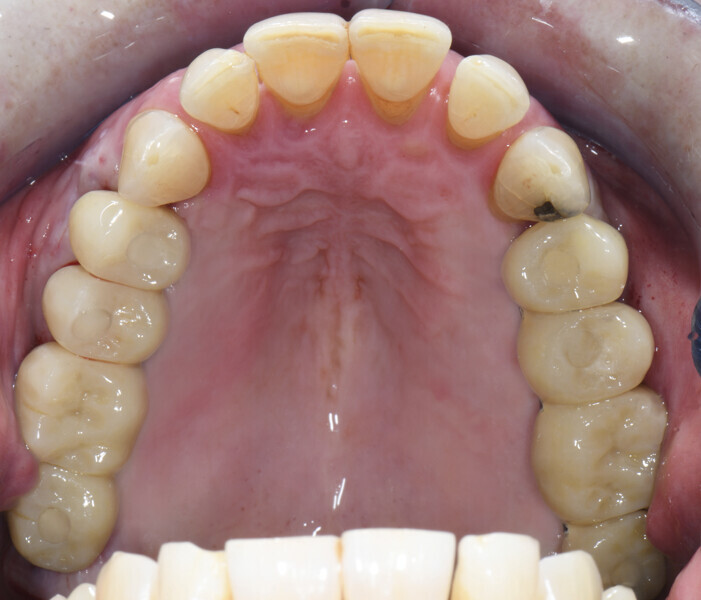

After a healing period of six months (Fig. 6), an intra-oral scan was performed at abutment level together with a scan of the existing temporary bridges in relation to the opposing arch (Figs. 7–11).